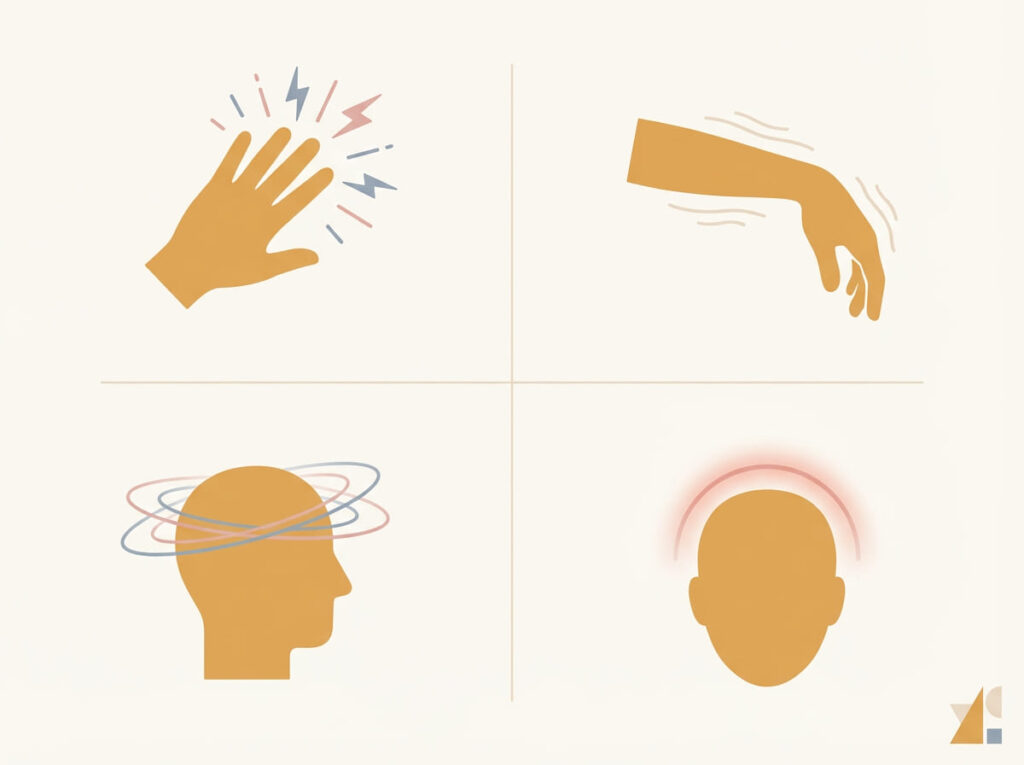

立ち止まるべきサイン

音ではなく、症状のセットで判断します。

- しびれ

- 脱力

- めまい

- 視覚異常

- 強い頭痛

- 外傷後に出現

これらの症状がある場合、「音の問題」ではなく神経や血管の評価が優先されます。